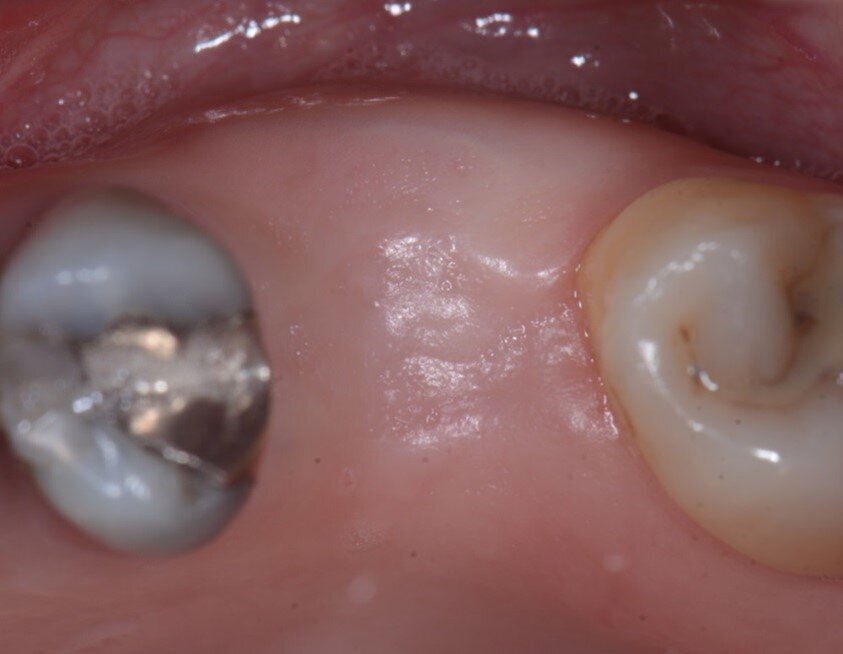

La CBCT dopo 4 mesi ha mostrato il mantenimento della corticale vestibolare (Figg. 7a, 7b), e anche un aumento della dimensione bucco-linguale (Fig. 8). Sul lato palatale, dove il sito è guarito naturalmente, la parete palatale ha subito un normale rimodellamento. Le immagini CBCT mostrano chiaramente la capacità della lamina corticale di inibire il riassorbimento della corticale buccale e di sostituirla o sostenerla. Ciò suggerirebbe che la lamina potrebbe essere utilizzata al posto di una membrana D-PTFE per ottenere un risultato ancora migliore rispetto alla classica tecnica di inibizione periostale, considerando anche che la lamina si integra nel sito8, 9 e non richiede una procedura di rientro. La guarigione è avvenuta senza complicazioni e il volume osseo creato era sufficiente per posizionare un impianto standard da 4,1 mm (Figg. 9, 10).

Fig. 8 - Guarigione a 4 mesi

Fig. 9 - Rientro a 4 mesi.